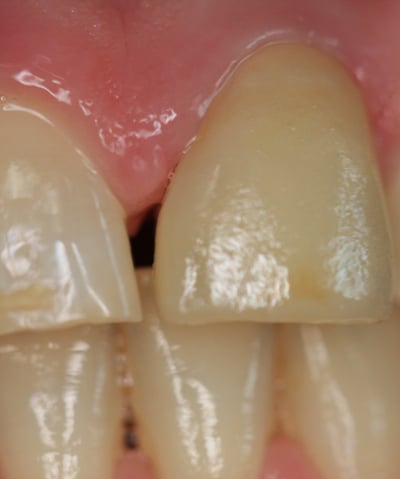

Corona Incongrua

Condizioni Iniziali

Moncone non ritentivo

Un paziente si è presentato alla nostra attenzione con un problema di decementazione ripetuta della corona su un incisivo centrale superiore (dente 21). Oltre all'evidente instabilità protesica, la corona mostrava una discrepanza estetica marcata rispetto ai denti naturali adiacenti, compromettendo l'armonia del sorriso.

Corona incongrua: non solo non si armonizzava con i denti circostanti, ma risultava anche inadeguata dal punto di vista funzionale.